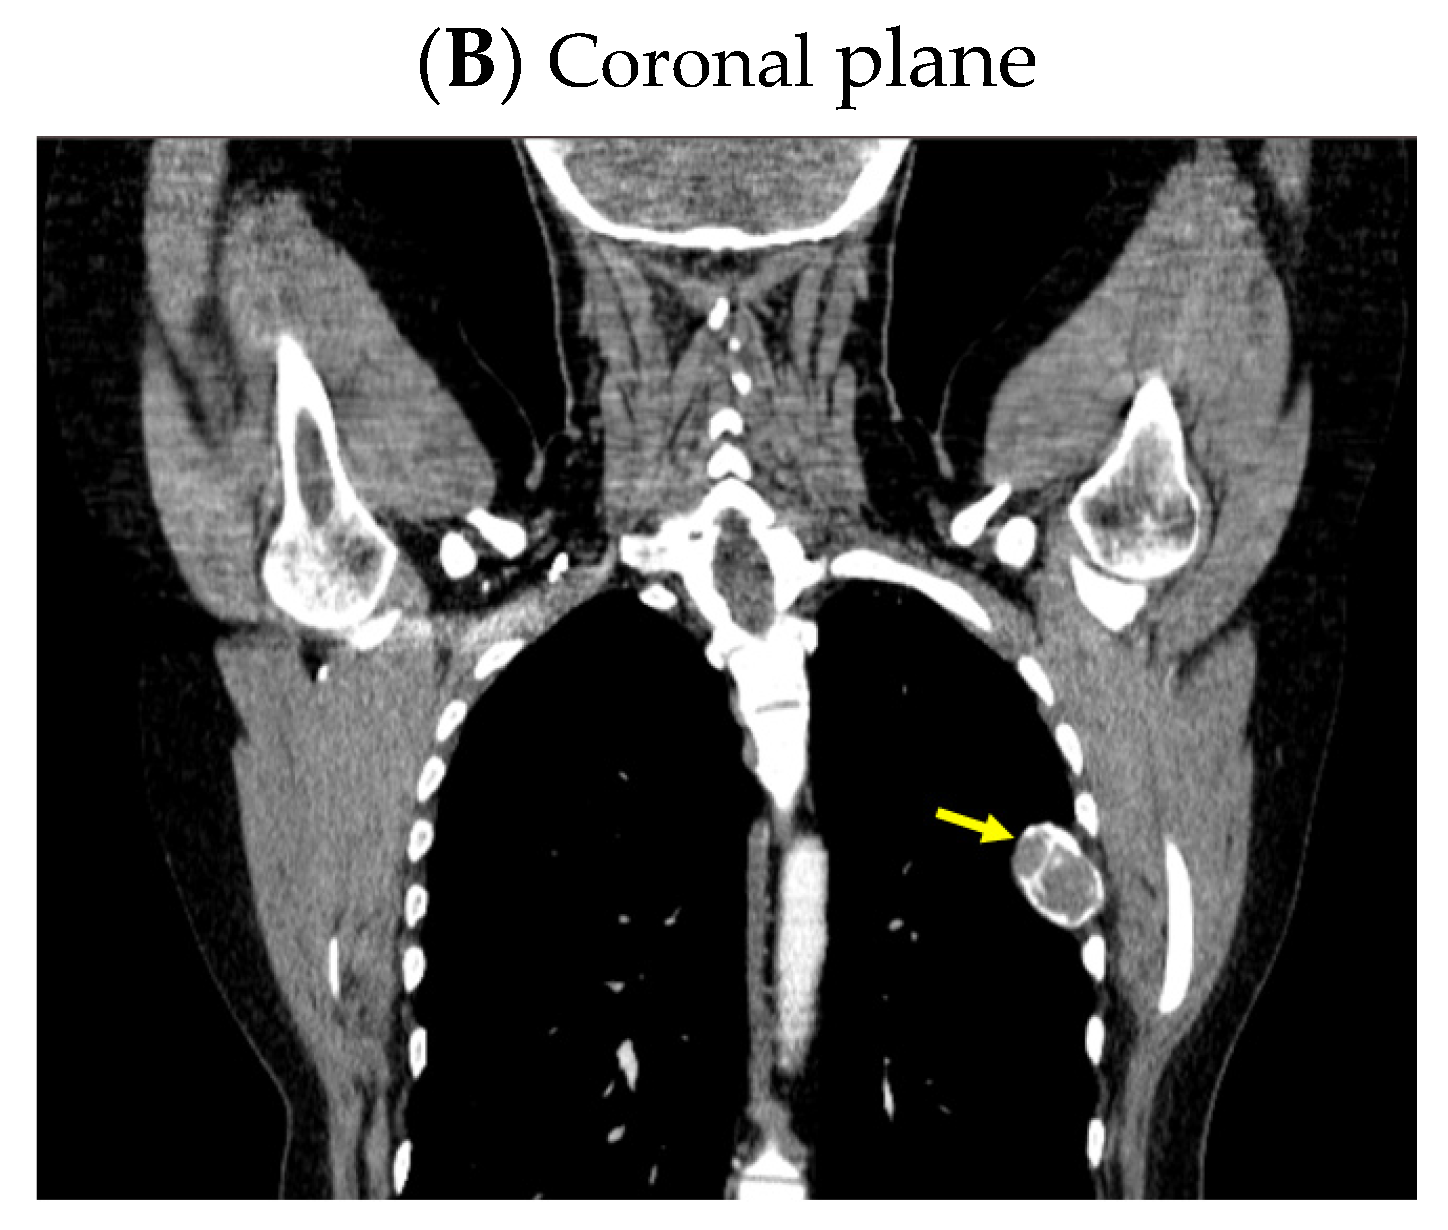

A pelvis CT scan confirmed the osteolytic lesions of the ischium and of the left coxal bone adjacent to the acetabular fossa, measuring 1.97 by 3.29 cm and 1.14 by 1.71 cm, respectively (brown tumors) (Figure 6).

Figure 6.

Pelvis CT scans showing other brown tumors: (A) osteolytic lesion of the left coxal bone adjacent to the acetabular fossa of 1.14 by 1.71 cm (axial plane); (B) osteolytic lesion of the left ischium of 1.97 by 3.29 cm (axial plane).